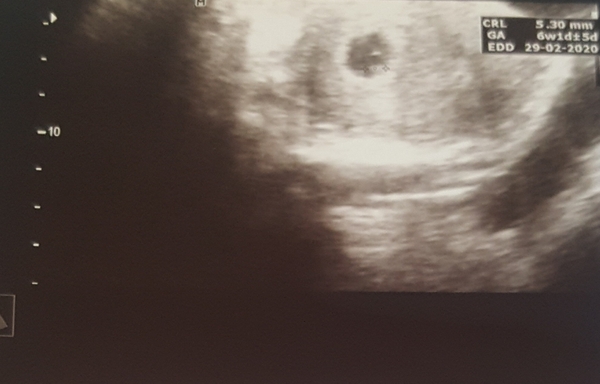

This is blurry as I took it with my phone but here's my scan from earlier in the week when I'd have been 6+2 or so. She said she could see the fetal pole and pointed out the amniotic sac. Actual embryo is too small at this stage I believe given its about the size of a grain of rice!